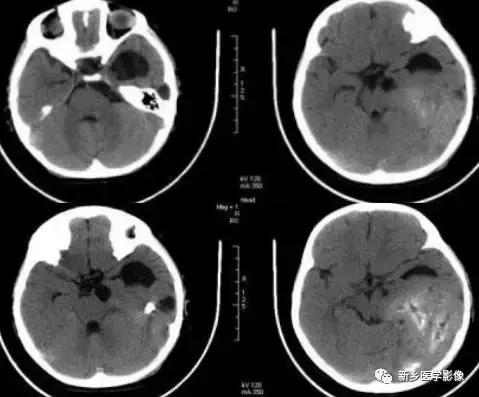

二、脑囊虫病

脑囊虫病慢性期,囊虫死亡以后,囊液逐渐被吸收,囊虫被机化,最后出现钙化。

钙化特点:多发、散在结节样钙化。钙化病灶通常较小、较圆、大小较均匀,少者单发或仅数个,多者可弥漫性分布于全部脑实质。